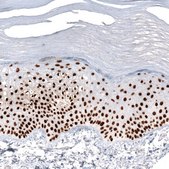

immunohistochemistry: 1:5000- 1:10000

The Human Protein Atlas project can be subdivided into three efforts: Human Tissue Atlas, Cancer Atlas, and Human Cell Atlas. The antibodies that have been generated in support of the Tissue and Cancer Atlas projects have been tested by immunohistochemistry against hundreds of normal and disease tissues and through the recent efforts of the Human Cell Atlas project, many have been characterized by immunofluorescence to map the human proteome not only at the tissue level but now at the subcellular level. These images and the collection of this vast data set can be viewed on the Human Protein Atlas (HPA) site by clicking on the Image Gallery link. We also provide Prestige Antibodies® protocols and other useful information.

• IHC tissue array of 44 normal human tissues and 20 of the most common cancer type tissues.